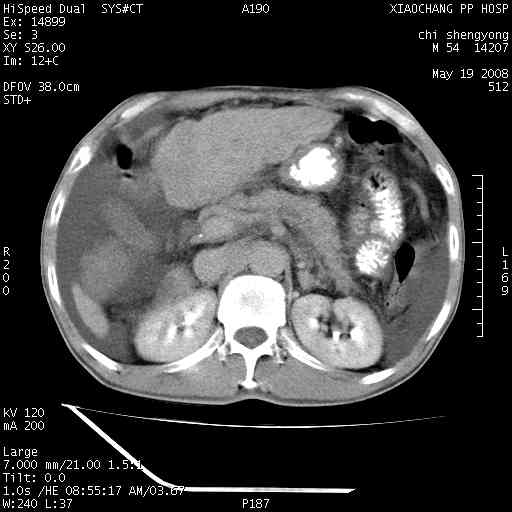

以下是引用zjzjr在2008-5-21 10:52:00的发言:[br]肝左叶巨块型肝癌伴门静脉左支瘤栓形成.肝硬化、腹水,胃底静脉曲张,脾术后改变。

以下是引用随光逐影在2008-5-21 16:20:00的发言:[br]1)肝左叶肝癌伴门静脉左支瘤栓形成,腹膜后淋巴结转移。2)肝硬化、腹水、胃底静脉曲张。3)胆囊炎。4)脾脏缺如,为切除术后所致。